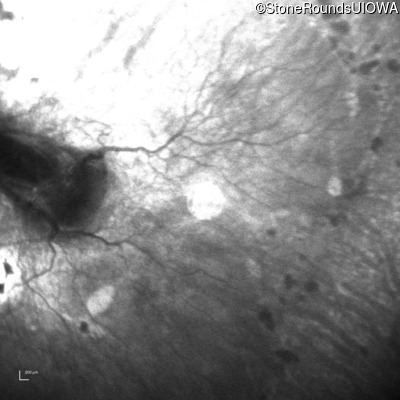

Infrared Fundus Photograph - Left - 20/250

Exemplar